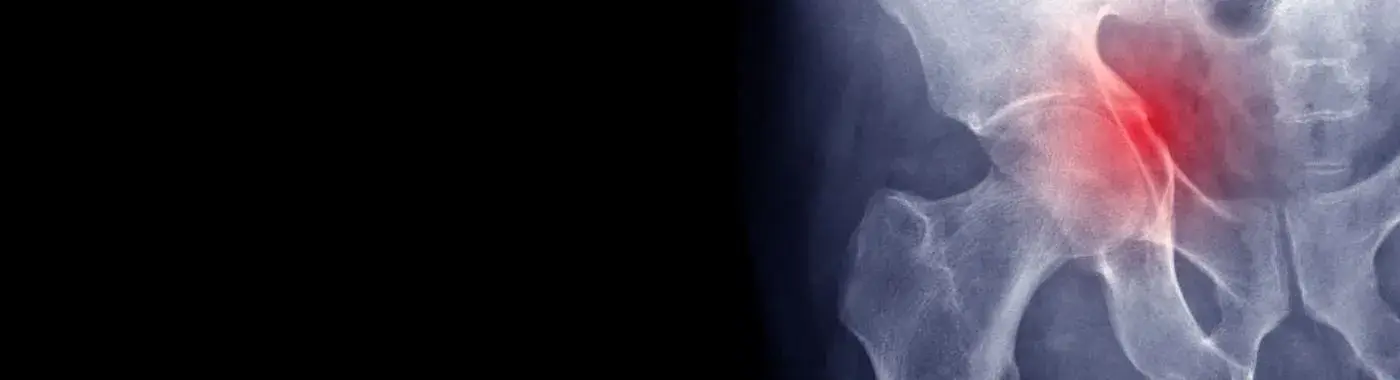

Acetabular Fractures - Causes, Symptoms, Diagnosis, Treatment, and Prevention

Acetabular Fractures: A Comprehensive Guide

Acetabular fractures are significant injuries that involve the acetabulum, the socket of the hip joint where the femur (thigh bone) fits. These fractures can lead to severe complications, including chronic pain, mobility issues, and long-term disability. Understanding acetabular fractures is crucial for both patients and healthcare providers, as timely diagnosis and appropriate treatment can significantly improve outcomes.

Acetabular fractures refer to breaks in the acetabulum, the cup-shaped structure of the pelvis that forms the hip joint. These fractures can occur in various patterns and may involve one or more parts of the acetabulum. They are often the result of high-energy trauma, such as car accidents or falls from significant heights, but can also occur in lower-energy situations, particularly in older adults with weakened bones.